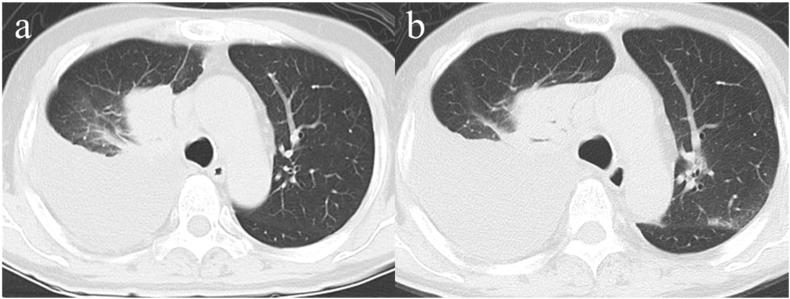

A 67-year-old man with stage IV B lung adenocarcinoma was treated with pembrolizumab. The patient was admitted to the hospital because of influenza on the day of the second cycle of pembrolizumab treatment. He was diagnosed with pneumonia and was treated with antiviral drugs and steroids. However, the patient eventually died. In this case, treatment with immune checkpoint inhibitors might have affected the immune response caused by influenza virus infection, that might have caused lung injury, which is an immune-related adverse event (irAE). Hence, it is important that, caution should be taken to prevent transmission of viral infection, and Therefore, it is important to prevent viral infections, but caution should also be paid to the possibility that infections may cause irAEs in patients with lung cancer.

一名67岁的IV B期肺腺癌男性患者接受了派姆单抗治疗。在派姆单抗治疗的第二个周期当天,患者因流感入院。他被诊断为肺炎,并接受了抗病毒药物和类固醇治疗。然而,患者最终死亡。在这种情况下,免疫检查点抑制剂治疗可能影响了流感病毒感染引起的免疫反应,这可能导致了肺损伤,这是一种免疫相关不良事件(irAE)。因此,重要的是要注意预防病毒感染的传播,所以,预防病毒感染很重要,但也应注意感染可能在肺癌患者中引起irAE的可能性。